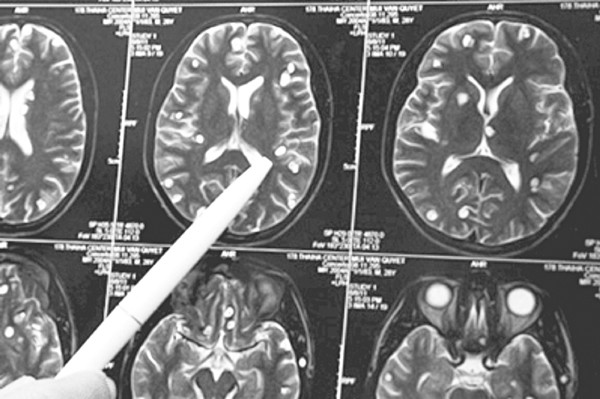

Nếu bị ấu trùng sán lợn ký sinh tại não, chụp cắt lớp CT-scanner có thể phát hiện thấy nang ấu trùng sán ở trong não; đó những nốt dịch có chấm mờ lệch tâm, kích thước khoảng từ 3 - 5mm, có nốt to hơn và có thể bị vôi hóa; khi chụp hình cộng hưởng từ MRI (magnetic resonance imaging) sẽ cho độ chính xác cao hơn nhưng cần cân nhắc để có chỉ định trong từng trường hợp cụ thể.

Nang ấu trùng sán lợn ký sinh ở não